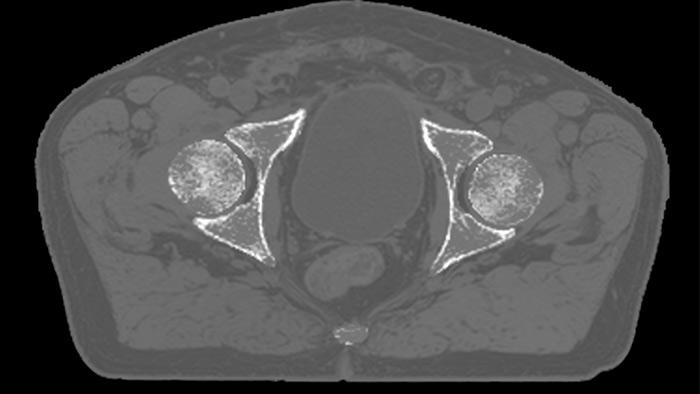

MRCAT Pelvis